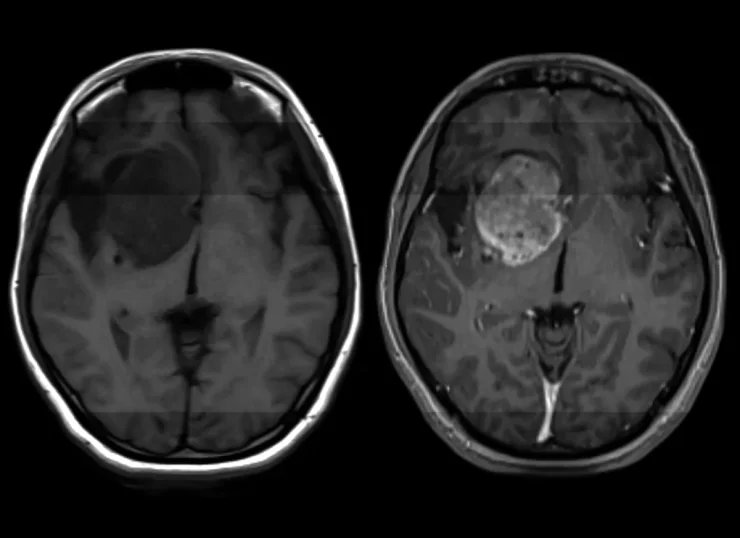

Una nuova scoperta nella patologia del glioblastoma – il tipo di tumore cerebrale più comune, attualmente incurabile – è stata fatta, aprendo la possibilità di un futuro trattamento che potrebbe essere semplice come prendere una pillola.

Ogni anno, più di 14.000 persone solo negli Stati Uniti riceveranno una diagnosi di glioblastoma, un tumore cerebrale aggressivo, imprevedibile e non prevenibile. Ognuno di questi nuovi pazienti vivrà in media da 12 a 18 mesi in più – senza trattamento, può essere molto meno – e solo uno su 20 sarà ancora vivo dopo cinque anni.

“Il glioblastoma è una malattia devastante. Essenzialmente non esiste una terapia efficace”, ha dichiarato Hui Li, ricercatore nel Dipartimento di Patologia della Scuola di Medicina dell’Università della Virginia, in un comunicato questa settimana. Ma già nel 2020, Hui e i suoi colleghi avevano compiuto un primo passo verso la scoperta di una cura: hanno identificato l’oncogene che scatena lo sviluppo del glioblastoma.